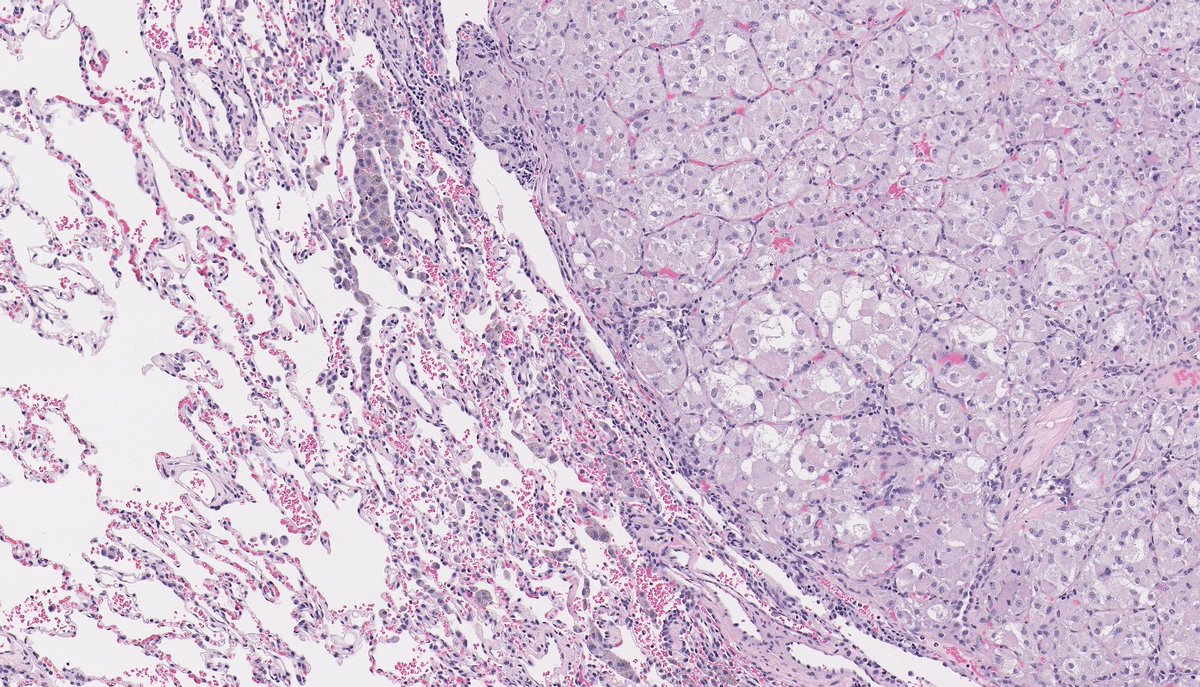

Anatomical Pathologist - UBC #BSTpath #GYNpath